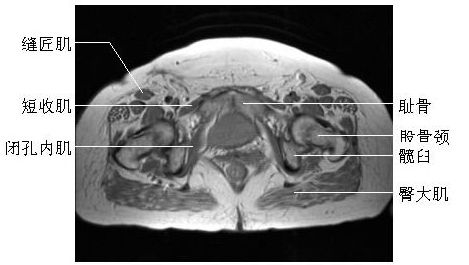

髋关节横断面(二)